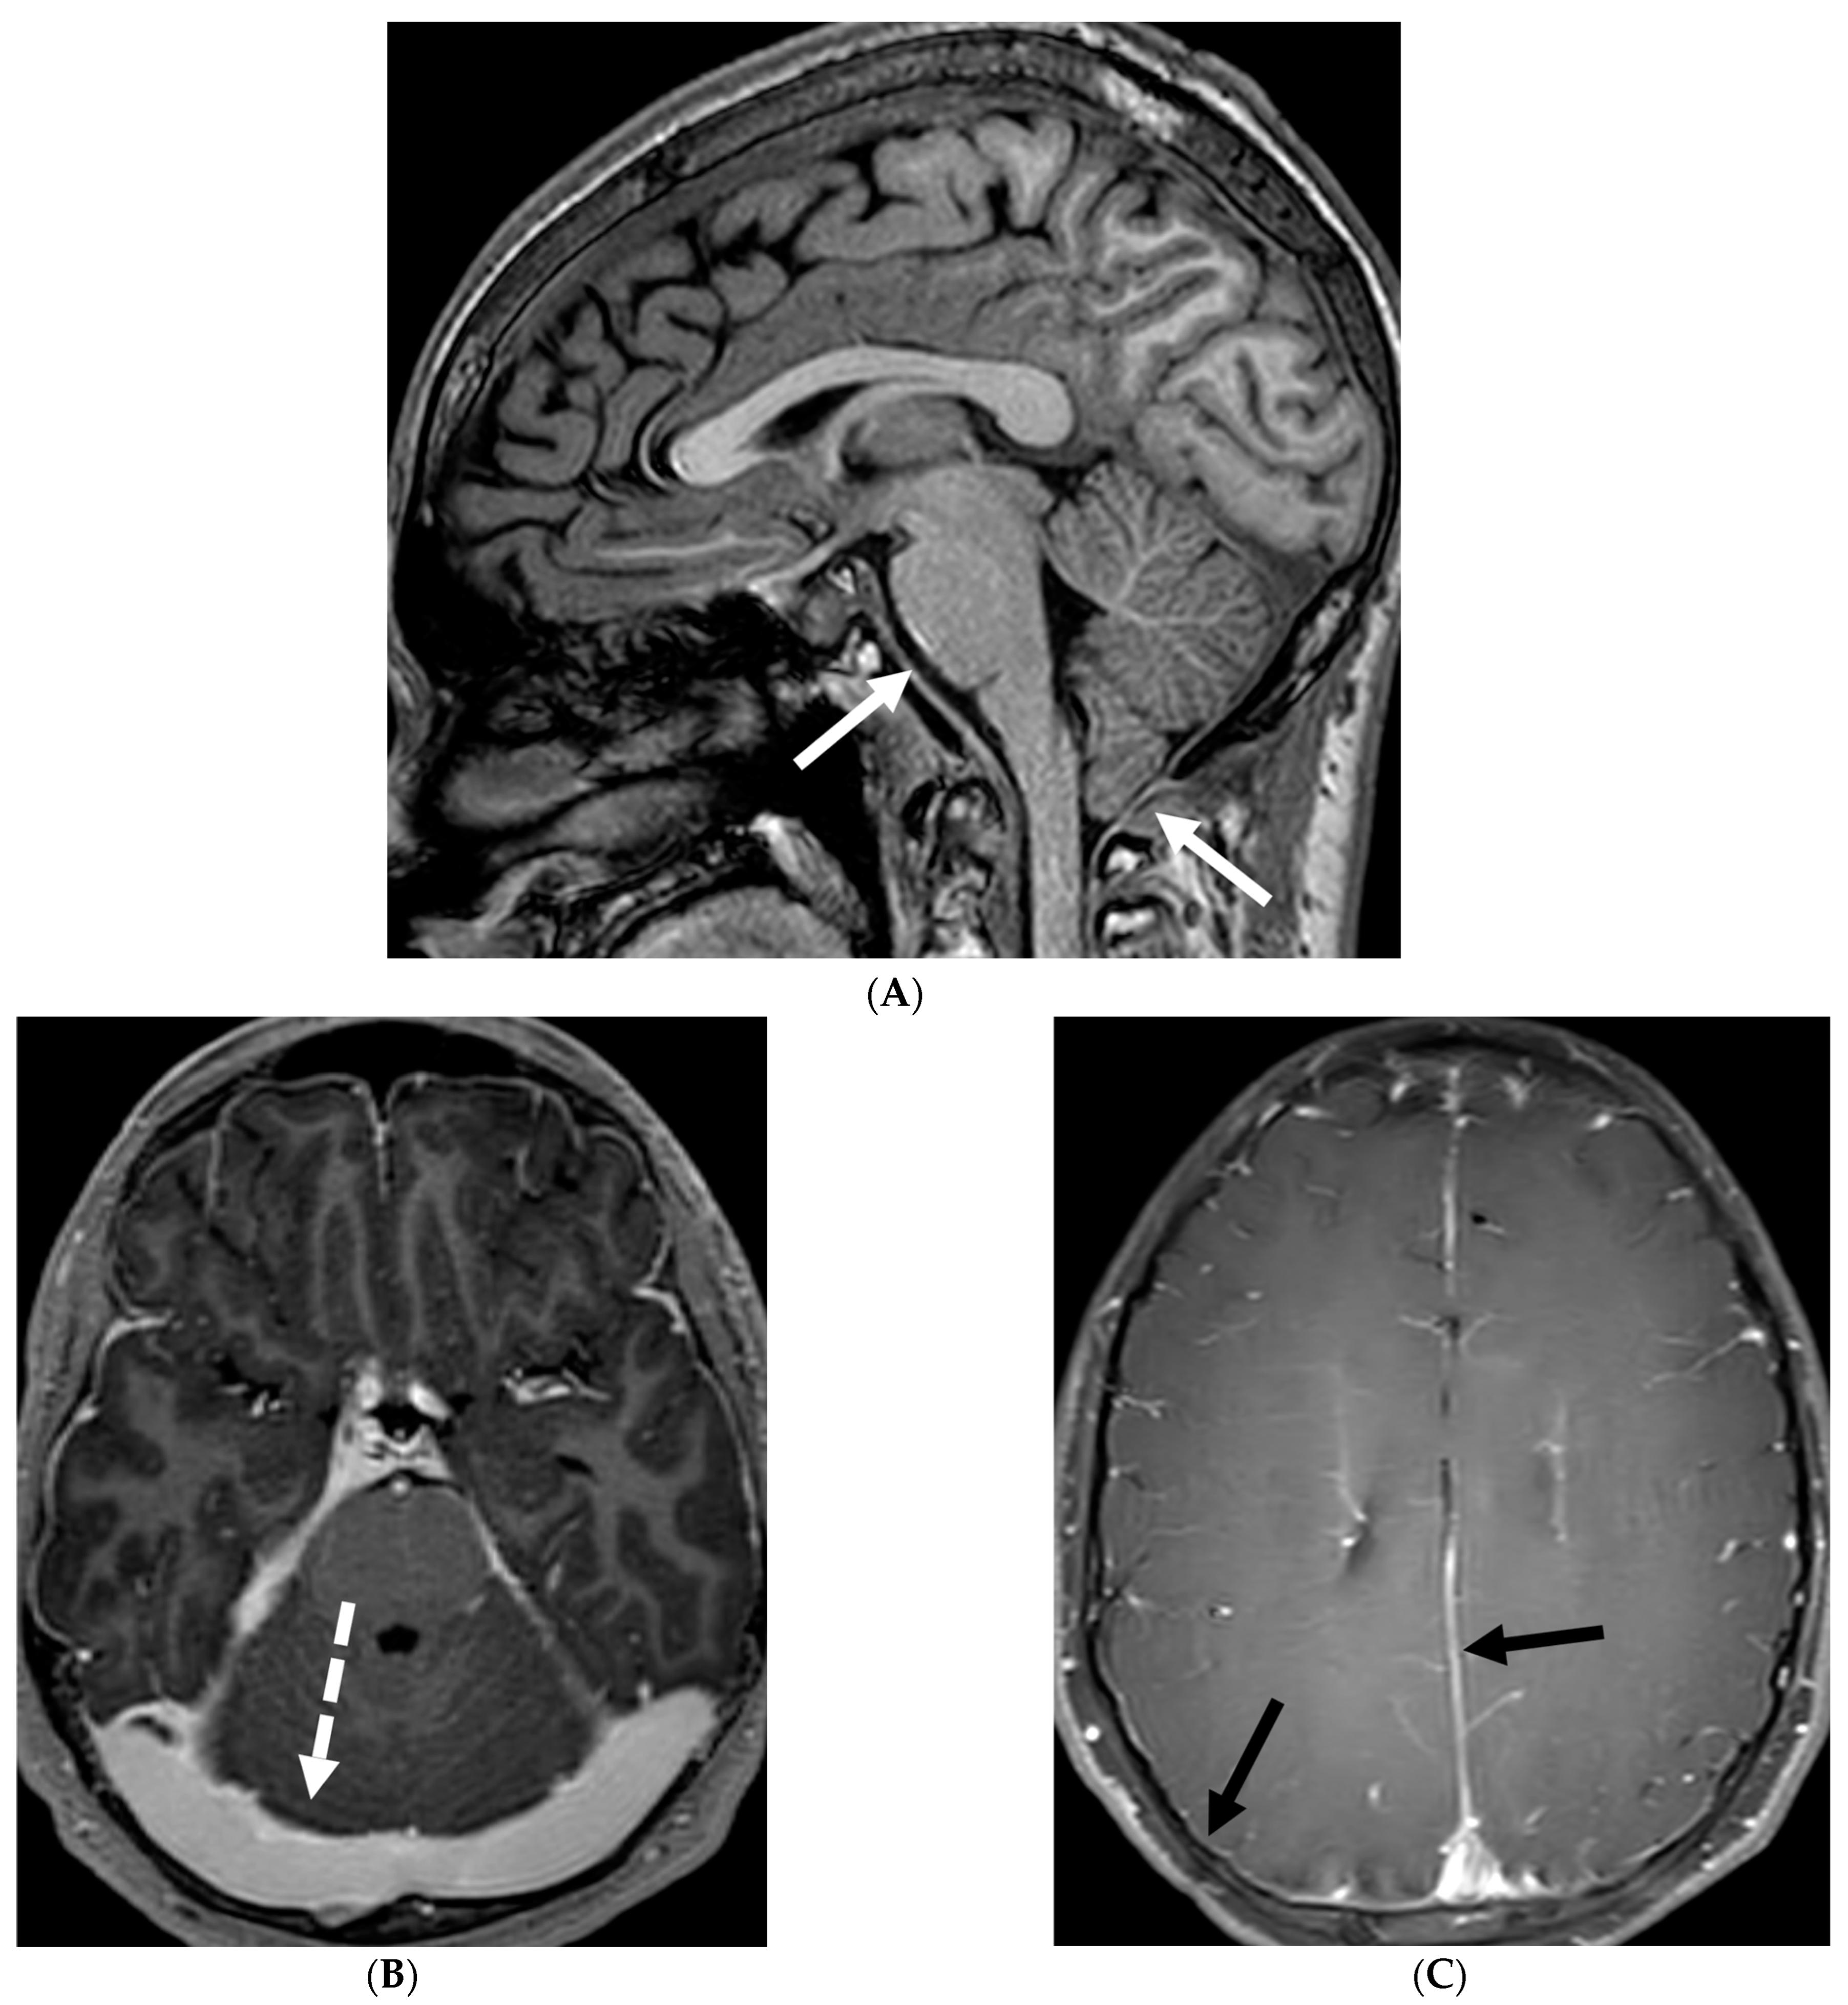

3.2. Neurosarcoidosis

Sarcoidosis is a systemic inflammatory disorder characterized by non-caseating granuloma formation [10,11,12]. Neurosarcoidosis (NS) is uncommon, detected on imaging studies in 15% of the patients, out of which only one-third of them present with clinical symptoms [10,13]. Granulomas, a hallmark of sarcoidosis, can infiltrate cerebral parenchyma, brain vasculature, and cranial nerves [14,15]. Parenchymal involvement leads to motor or sensory deficits, whereas predominant meningeal and subarachnoid involvement leads to cranial nerve deficiencies and vision changes [11]. Contrast-enhanced MRI of the brain and/or the spine is currently considered the standard of care for initial work-up and follow-up in NS [16].

Nodular or diffuse LME, primarily involving the basal meninges, is the most typical finding. It can further spread into the parenchyma via the perivascular spaces [17]. Most cases show focal involvement and are hypointense on T2WI with variable post contrast enhancement [18,19]. Nonenhancing white matter lesions (NEWM), although common, have been shown to have no symptomatic correlation [18]. Optic and facial nerves are frequently involved (Figure 3). The diagnosis of optic neuritis is crucial and regarded as an emergency due to its unfavorable prognosis if not promptly treated [20]. Occasionally [18,21,22], small vessel ischemia related cerebrovascular events occur which manifest clinically with progressive encephalopathy rather than a distinct large vessel stroke [13]. Other rare but important findings include spinal cord and hypophyseal involvement [23]. The mainstay of treatment for CNS sarcoidosis involves corticosteroids to suppress inflammation.

Figure 3.

18-year-old presented with headache, persistent vomiting and weight loss. History of sarcoidosis diagnosed 2 years ago. Axial Fluid Attenuated Inversion Recovery (FLAIR) (A), Axial T1 post contrast (B), Axial T1 inversion recovery post contrast (C) and Coronal Positron Emission Tomograpy (PET) scan (D): There is a heterogeneously enhancing ill-defined area of T2/FLAIR hyperintensity involving the medial aspect of the left globus pallidus (arrows), anterior aspect of the left thalamus and left hypothalamic region. Diffuse enhancement of the basal meninges, tentorium, throughout perisylvian sulci (arrow heads), along the infundibulum, and posteriorly at the craniocervical junction. There is also enhancement along optic nerve sheath (dashed arrows). Features are highly consistent with extensive neurosarcoidosis given the previous history of thoracic sarcoid. PET scan from 2 years earlier demonstrating avid uptake of radiotracer (curved arrows). Radiologically, the differential diagnosis includes tuberculosis and metastatic process. Patient made complete recovery after treatment for sarcoid.